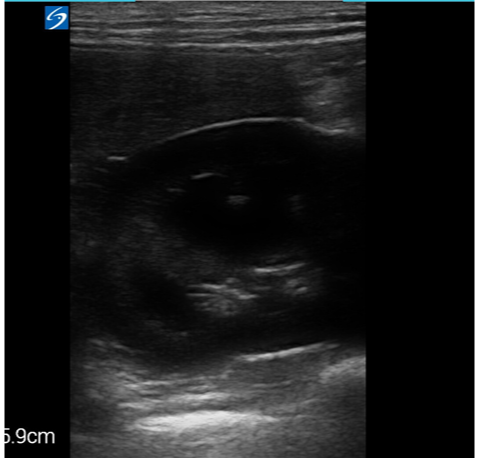

Probes

This machine has some great positives, robust, small, portable, light and quick start up time. The image quality on the linear probe is great (L38v) however with a frequency range of 10-5MHz it only reaches a depth of 9cm. The phased probe (P21v) image unsurprisingly with a frequency of 1-5MHz has less resolution, but does reach an impressive depth of 32cm. The functions are clearly labelled apart from recording a clip you have to hold the save button down for a few seconds and to change from 2D to M-mode you have to hold down the 2D button for a few seconds. Individual clips can be up to 30 seconds long.

Images from the iViz